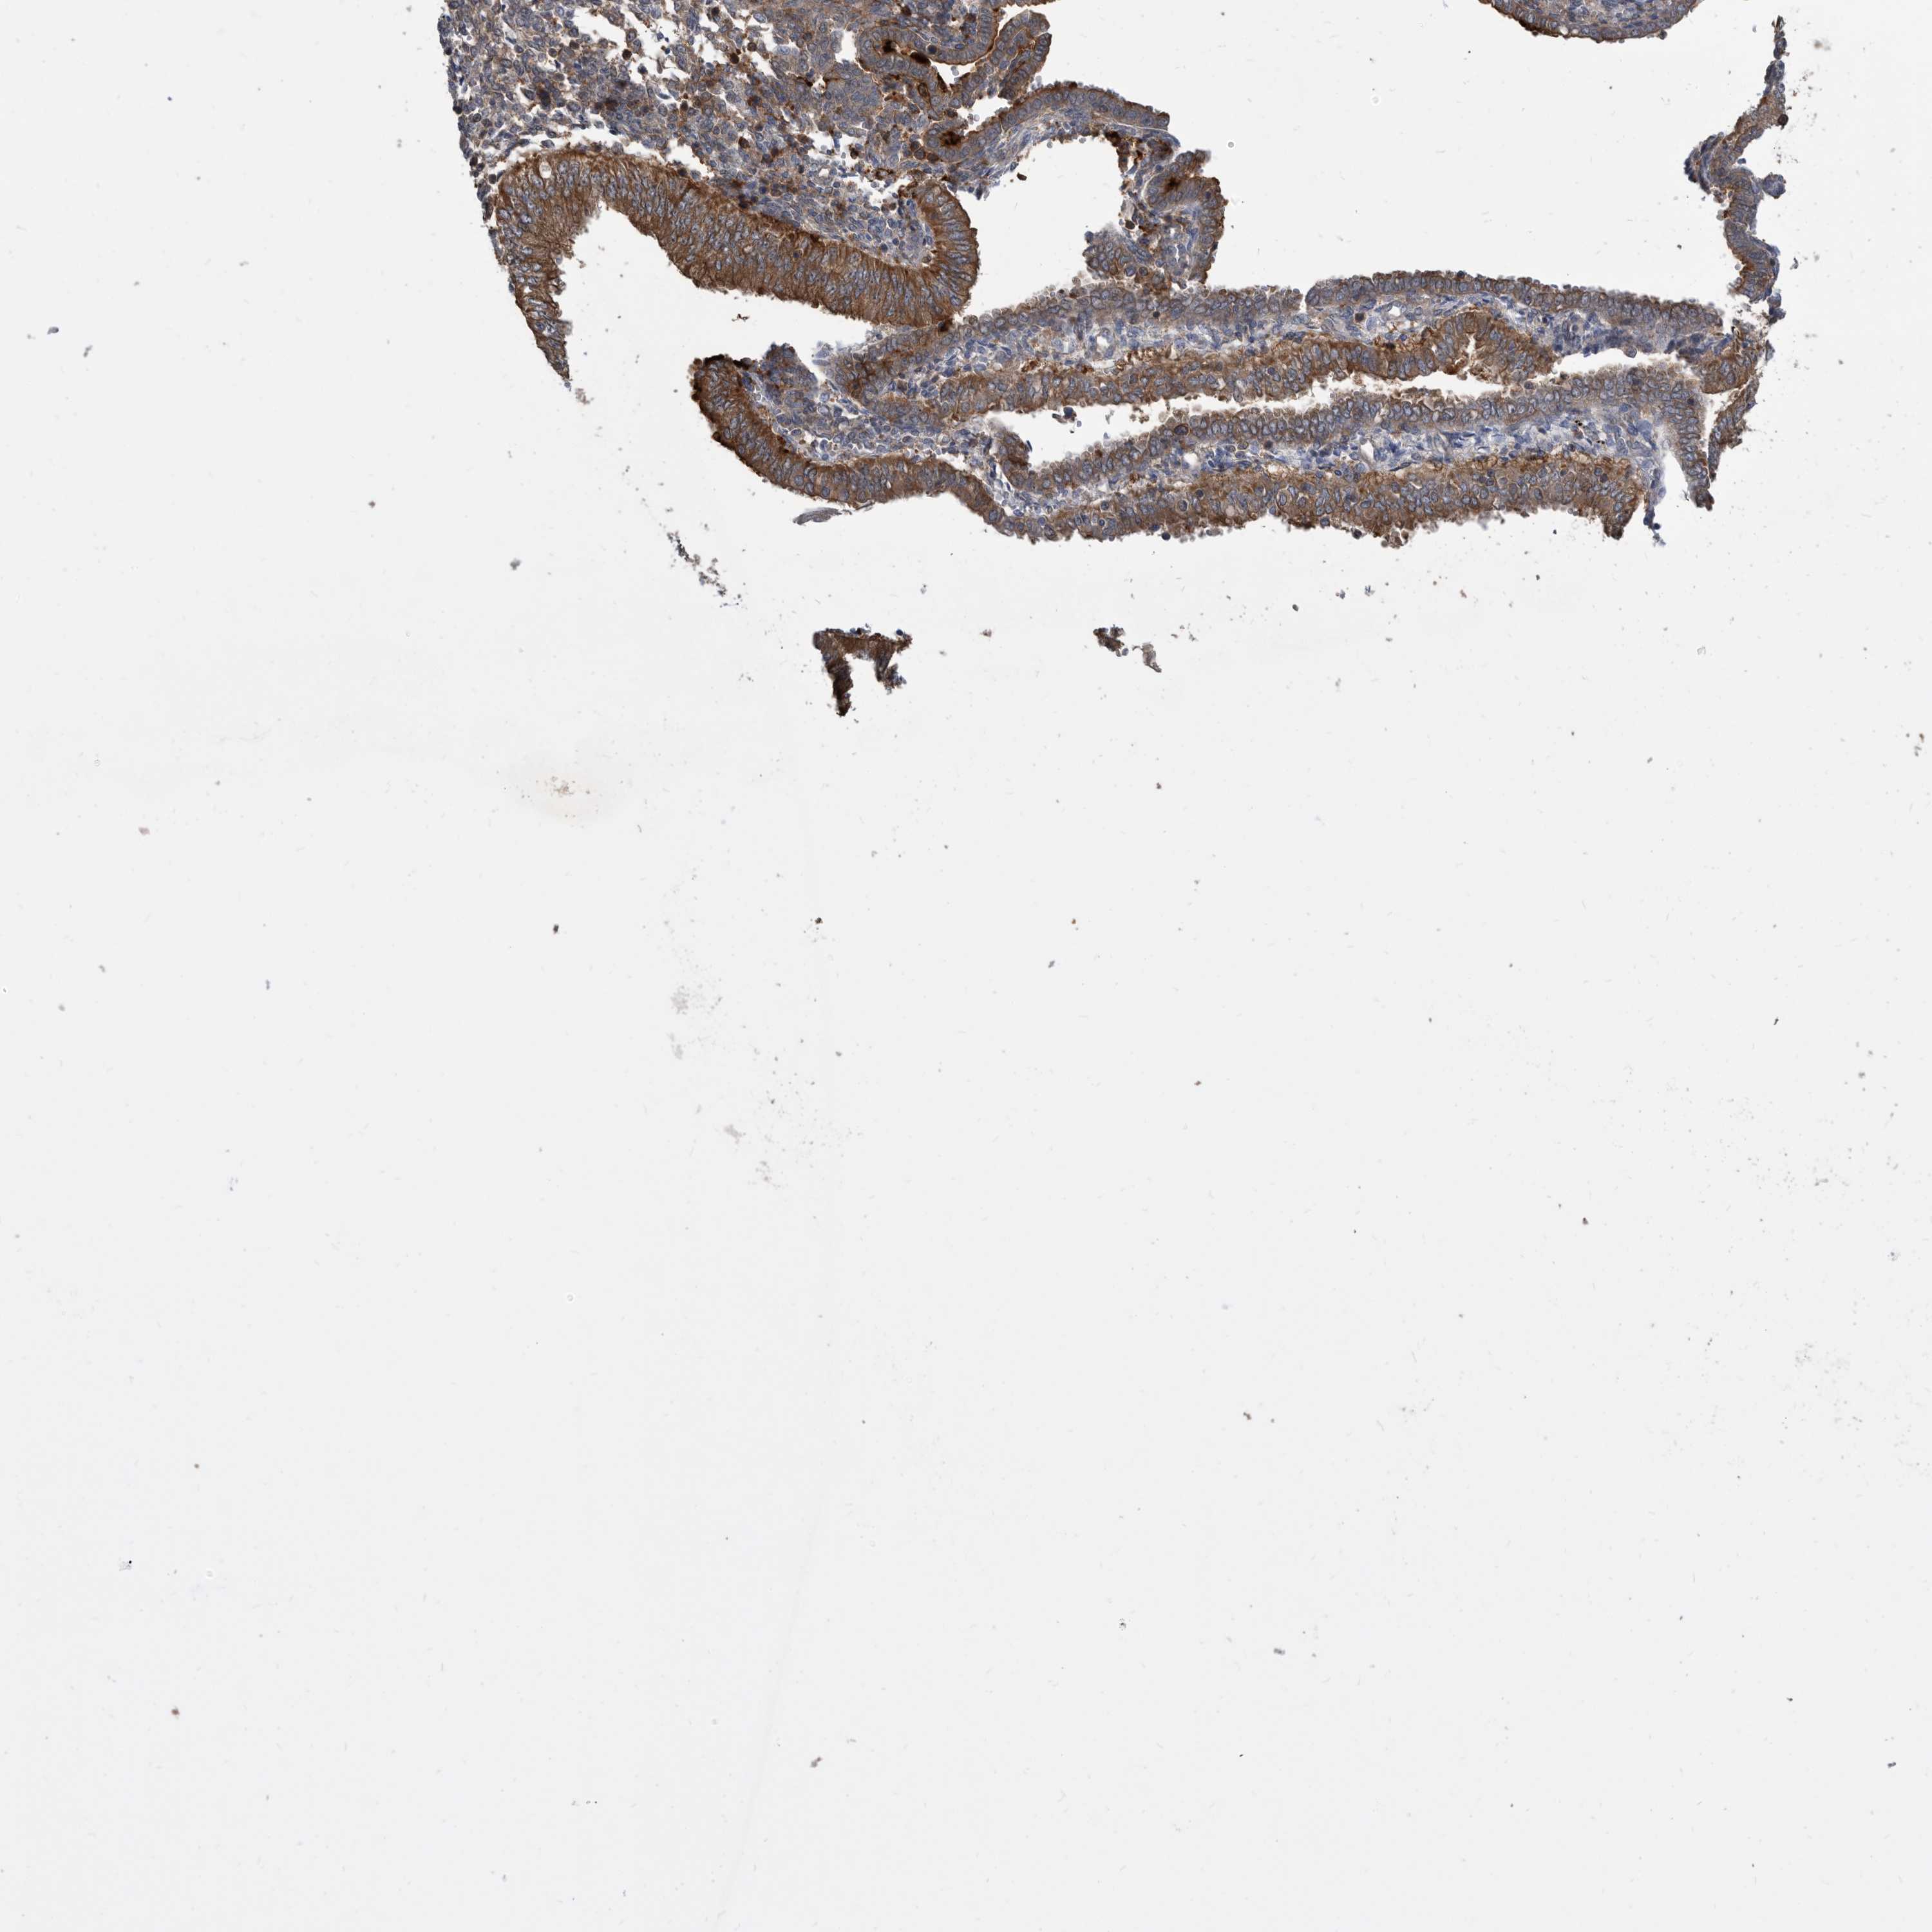

ENDOMETRIAL CANCER - Protein expressioni

A mouse-over function shows sample information and annotation data. Click on an image to view it in a full screen mode. Samples can be filtered based on level of antibody staining by selecting one or several of the following categories: high, medium, low and not detected. The assay and annotation is described here.

Note that samples used for immunohistochemistry by the Human Protein Atlas do not correspond to samples in the TCGA dataset.

Antibody stainingi

Antibody staining in the annotated cell types in the current human tissue is reported as not detected, low, medium, or high, based on conventional immunohistochemistry profiling in selected tissues. This score is based on the combination of the staining intensity and fraction of stained cells.

Each image is clickable and will lead to virtual microscopy that enables deeper exploration of all samples and also displays staining intensity scores, fraction scores and subcellular localization as well as patient and tissue information for each sample.

Antibody HPA029700

Antibody HPA029701

Antibody HPA029702

Antibody HPA029703

Staining

High

Medium

Low

Not detected

Intensity

Strong

Moderate

Weak

Negative

Quantity

>75%

75%-25%

<25%

None

Location

Nuclear

Cytoplasmic/membranous

Cytoplasmic/membranous,nuclear

Adenocarcinoma, NOS

Adenocarcinoma, metastatic, NOS